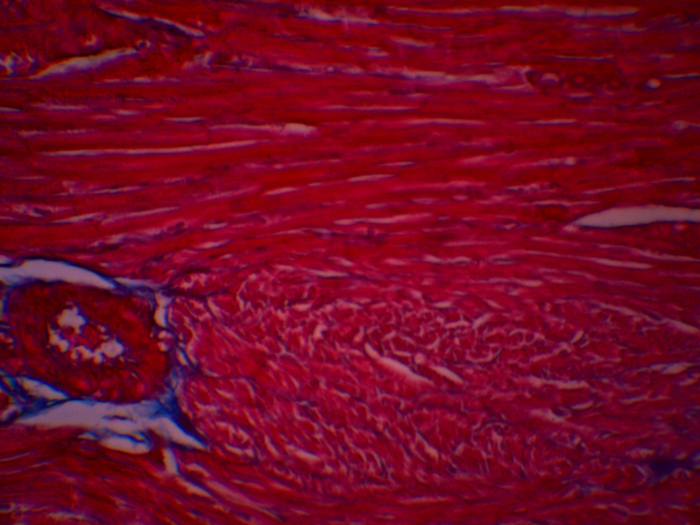

Trichrome Masson Staining of Rat Heart Tissue